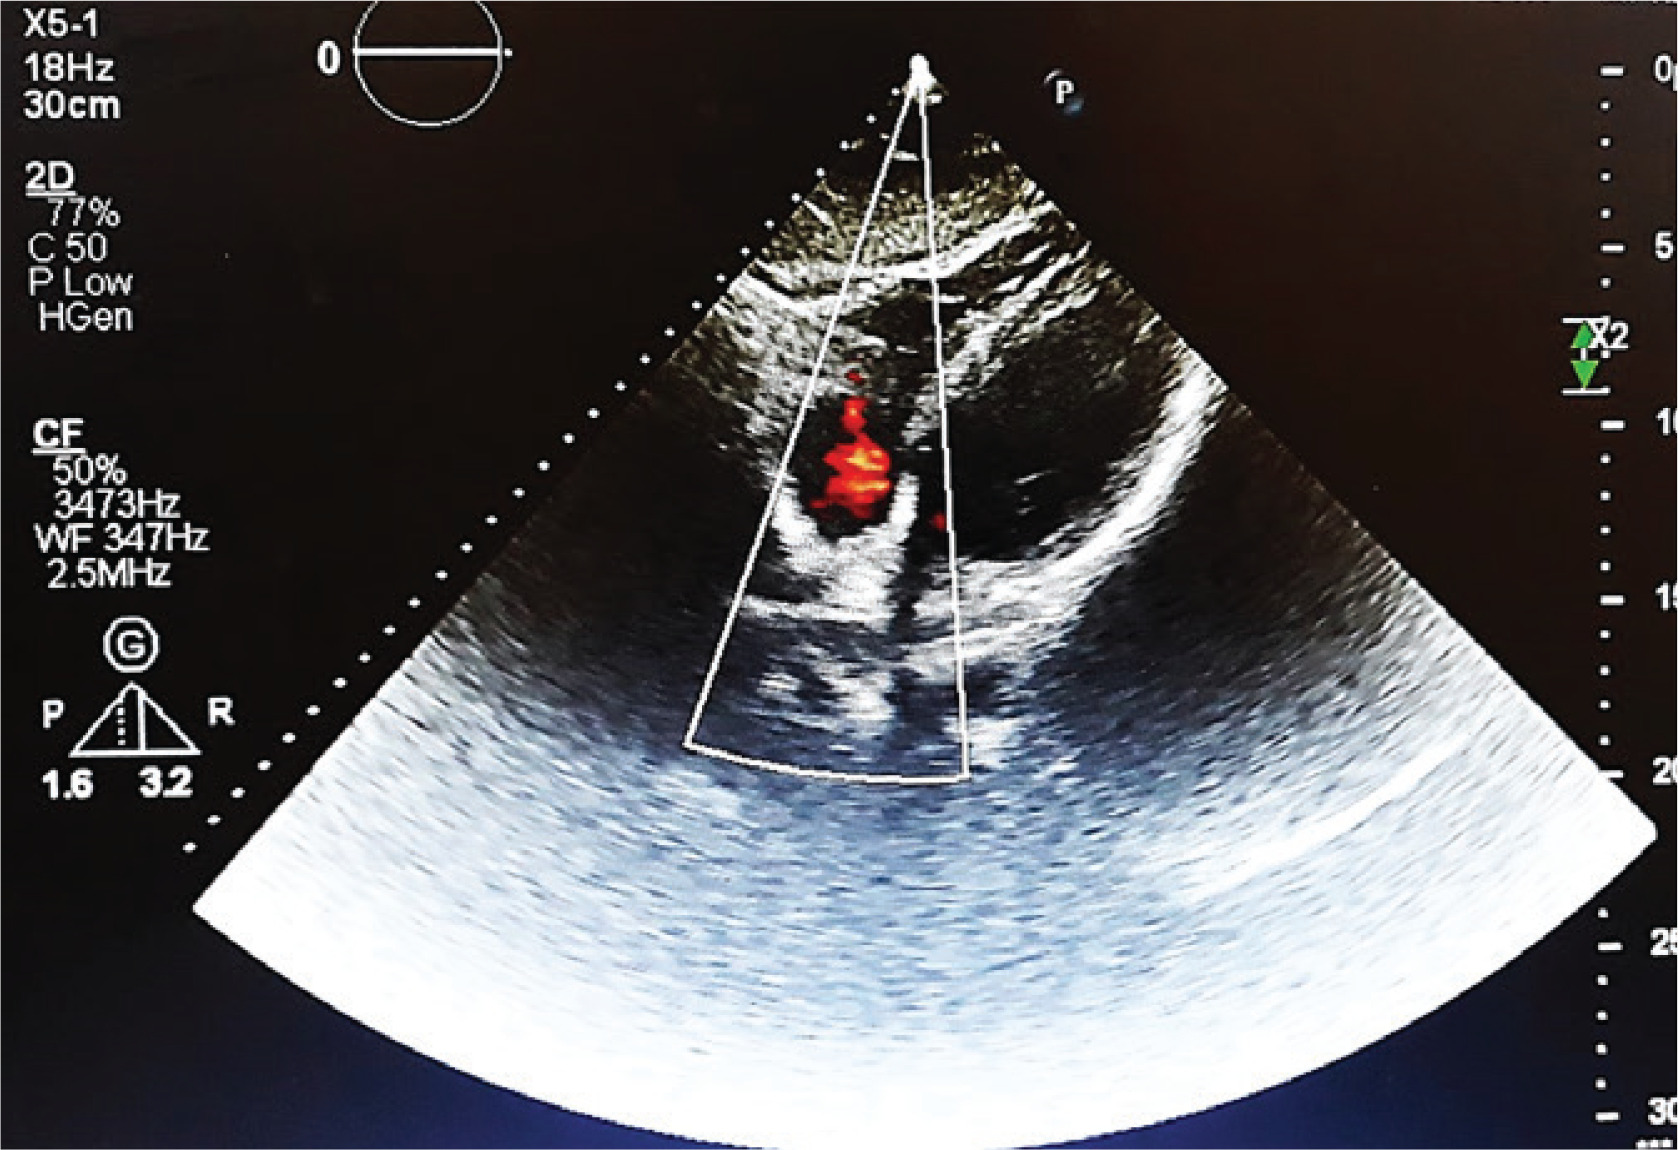

Transthoracic echocardiography (TTE) revealed a 2.8×2.2 cm partially mobile mass attached to the RV free wall, without involvement of the tricuspid valve. The mass demonstrated antegrade flow, supporting a thrombus rather than valvular vegetation. Cardiac function was preserved, with an ejection fraction of 55%, no regional wall motion abnormalities, and normal diastolic filling velocities, suggesting that the thrombus was primarily related to vasculitis rather than underlying cardiac dysfunction (Figure 2). Consecutive sets of blood cultures were obtained to rule out infective endocarditis, all of which yielded negative results. Rheumatoid factor (RF), viral serologies (e.g. HIV, hepatitis) and antiphospholipid syndrome (APS) diagnostic panel (e.g. lupus anticoagulant, anticardiolipin, antibodies, and anti-beta-2 glycoprotein 1 antibodies) were also negative. Differential diagnoses for the RV mass included intracardiac thrombus secondary to BD-related vasculitis, non-bacterial thrombotic endocarditis (NBTE), and embolization from lower limb thrombi. Given negative blood cultures, absence of malignancy markers, and no clinical evidence of deep vein thrombosis, vasculitis-related thrombus was considered most likely. However, NBTE and thrombus embolization remain plausible and are discussed further in the Discussion section. Treatment was initiated with low-molecular-weight heparin (LMWH; enoxaparin 1 mg/kg twice daily) for suspected thrombus. Although the ESR was low (10 mm/h), this may reflect individual variation in inflammatory response. It may also have been attributable to the empiric antibiotics given during the prior hospitalization.

Figure 2

Transthoracic echocardiogram (four-chamber view) revealing a 2.8×2.2 cm irregular, mobile mass attached to the RV free wall